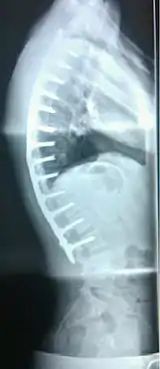

| Scheuermann's disease on lateral Xray of the T spine | |

Scheuermann's disease is a self-limiting skeletal disorder of childhood. Scheuermann's disease describes a condition where the vertebrae grow unevenly with respect to the sagittal plane; that is, the posterior angle is often greater than the anterior. This uneven growth results in the signature "wedging" shape of the vertebrae, causing kyphosis. It is named after Danish surgeon Holger Scheuermann.[3][4][5]

Scheuermann's disease is considered to be a form of juvenile osteochondrosis of the spine. It is found mostly in teenagers and presents a significantly worse deformity than postural kyphosis. Patients suffering with Scheuermann’s kyphosis cannot consciously correct their posture. The apex of their curve, located in the thoracic vertebrae, is quite rigid.

Diagnosis is typically by medical imaging. The degree of kyphosis can be measured by Cobb's angle and sagittal balance.